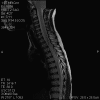

Representative images from the MR studies and specimen are illustrated below:

A. T1 |

B. T1+Contrast |

C. T1+Contrast |

D. T2 |

E. T1+Contrast |

Panel A to E are MR images. Panel F and G are taken from intraoperative cytologic preparation. Panel H to M are taken from frozen section. Panel N and O are from paraffin section. These sections are stained by hematoxylin-eosin stain. Panel P is immunohistochemistry for neurofilament proteins. Panel Q is stained by Luxol fast blue-Periodic acid Schiff (LFB-PAS) stain.

The segment of spinal cord at T3-T4 level is expanded and is accompanied by edema that runs from T2-T6. The expansion and edema is roughly symmetrical along the long axis of the cord. The expanded levels are isointense to the white matter of the spinal cord on T1-weighed images (Panel A). The edema is best demonstrated on T-weighed images (Panel B, C, and E). Patchy and poorly defined enhancement is demonstrated in the expanded areas (Panel D). The remaining levels of the spinal cord and the brain are free of abnormal changes.